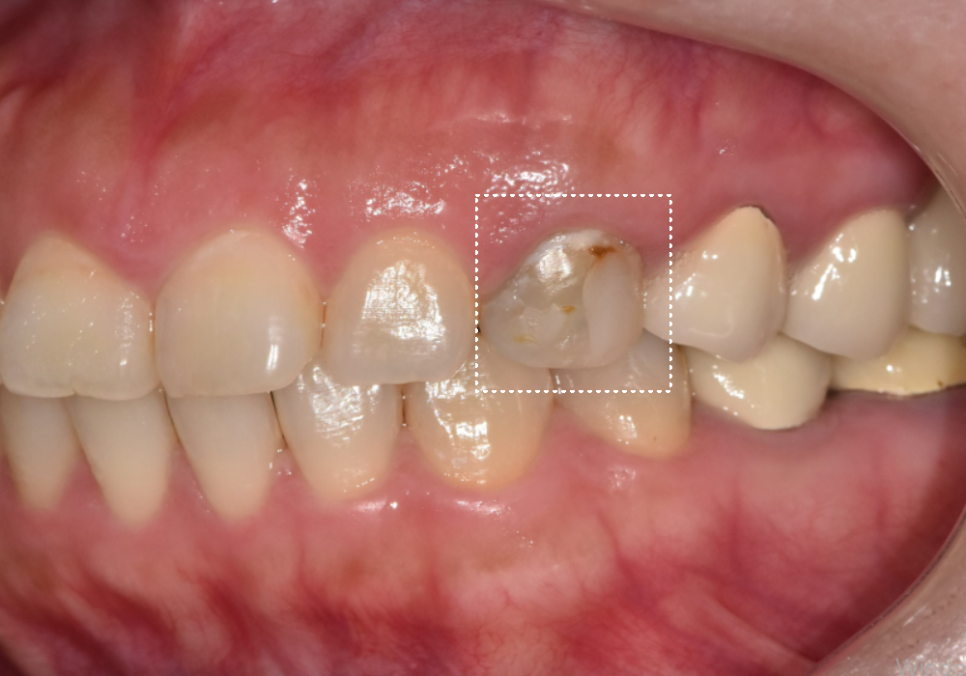

치료를 위해 치아를 다듬어보니

겉에서 보던 것보다

내부 변색된 모습이 확 티가 나죠?

251101

옆 치아들과 비교했을 때,

확실히 어둡고 탁한 색조가

치아 깊숙한 곳까지 배어 있는 모습인데요,

이처럼 내부 변색이 심할 때는

그냥 덮어 씌워 사용해서는 안 됩니다.

지르코니아는 특유의 투명도가 있어

안쪽의 어두운 색상이 겉으로

배어 나올 수 있기 때문에

특히나 신경 써야 하는데요.

그래서 저희는 크라운 내부에

'오팩(Opaque) 처리'를 더했습니다.

내부의 어두운 변색이 겉으로 드러나지 않도록

확실하게 차단막을 만들어주는 과정입니다.